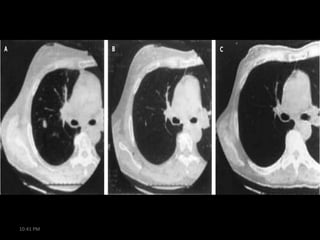

Paraneoplastic Cerebellar

Degeneration

• Laboratory evaluation

– diffuse cerebellar atrophy

months to years after onset on

head imaging

– CSF (early)

• increased lymphocytes

• slightly elevated protein and

IgG concentrations

• Pleocytosis resolves with time